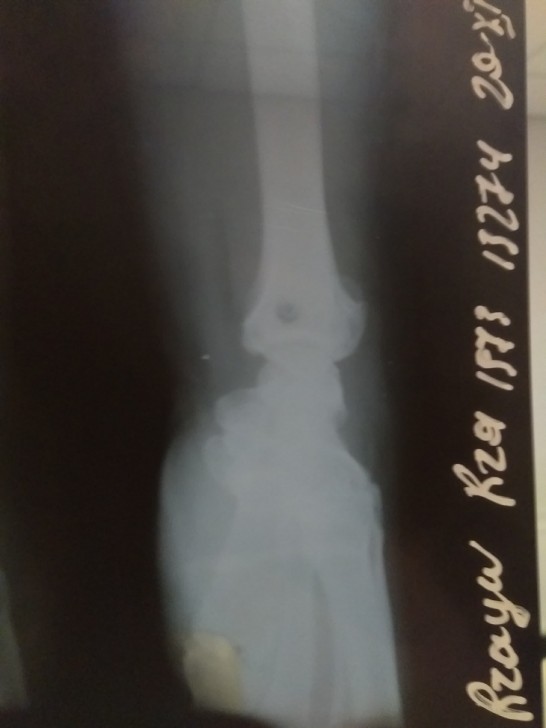

Qeyd edək ki, bir sıra KİV-lərdə guya təkcə T.Mirzəliyevin xəsarət alması haqda məlumat yayılıb. Lakin R.Rzayev də insident zamanı ağır xəsarət alıb. Onun sağ qolu biləkdən çatlayıb, sağ gözünün ətrafında xəsarət izləri var. Aktyorun qoluna 3 saylı Şəhər Klinik Xəstəxanasında gips qoyulub. R.Rzayev sabah tomoqrafiya olunması üçün başqa xəstəxanaya yaxınlaşacağını bildirib.